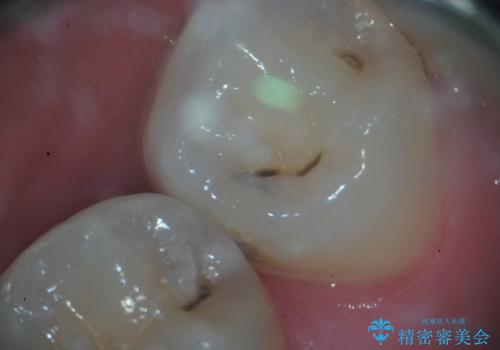

マイクロスコープ下でう蝕検知液を併用し、感染歯質のみを丁寧に除去しました。その後、適切な形態に形成を行い、精密な印象採得を行ってセラミックインレーを製作しました。

装着時には拡大視野でインレーの適合を確認しながら、ラバーダムも使用して確実な接着操作を行いました。